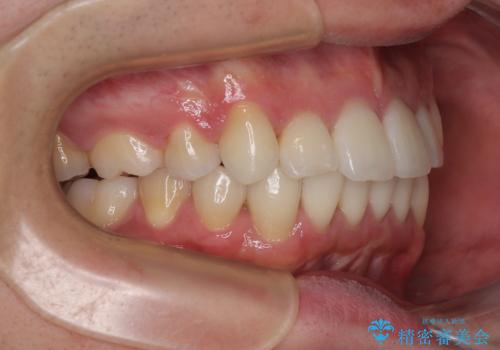

治療について

上顎のみの抜歯矯正であったため、治療期間が長期化することが予想されましたが、何とか3年弱の期間で想定通りの仕上がりで終えることができました。